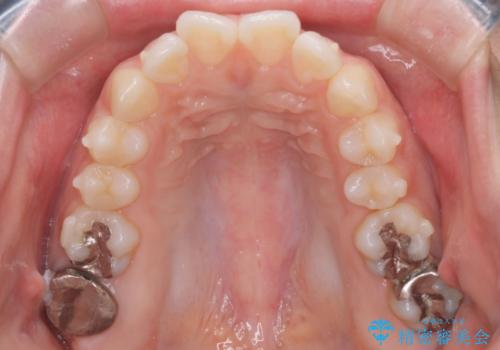

- 前歯が出ていることを主訴に来院された患者様です。

抜歯を希望されなかっため、臼歯部の遠心移動やIPRを行い配列を行っています。

抜歯をしていない矯正となるため、口元に大きな変化は認められません。